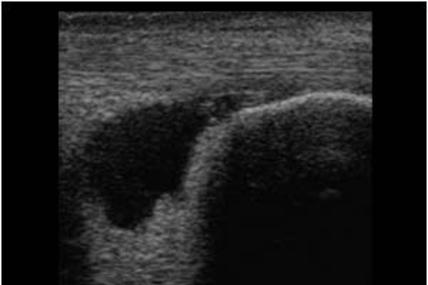

Achilles Tendon

Calcaneus

Retrocalcaneal Bursitis.